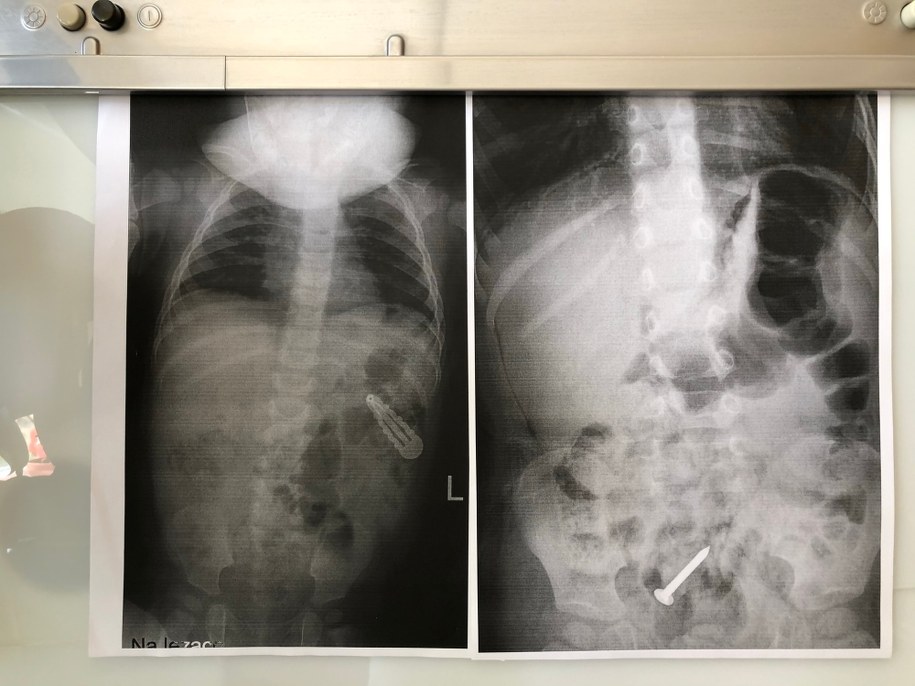

Dzieci połykają nie tylko magnetyczne klocki czy kulki. Różnorodność połkniętych przedmiotów zdumiewa: od gwoździ papowiaków, przez końcówki do wkrętarki, spinki do włosów, agrafki, klocki plastykowe, po monety i baterie.